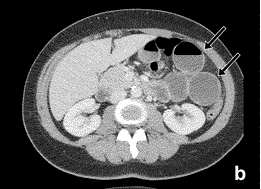

Article: Diagnosing internal herniation after laparoscopic Roux-en-Y gastric bypass: usefulness of systematically reviewing CT scans using ten signs